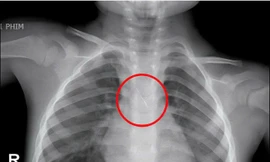

TPO - Bệnh viện Phụ sản – Nhi Đà Nẵng vừa tiếp nhận 2 trường hợp trẻ nhỏ hóc dị vật đường thở, đều liên quan đến các loại hạt thường gặp trong dịp Tết.